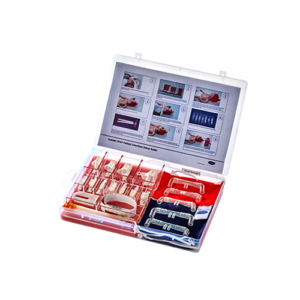

50-05-261, 50-05-113, 50-05-114, 50-05-115, 50-05-116

Maxflow Kids nasal cannula delivers precisely controlled, heated, and humidified air–oxygen mixtures at high flow rates to support spontaneous breathing during high flow oxygen therapy.